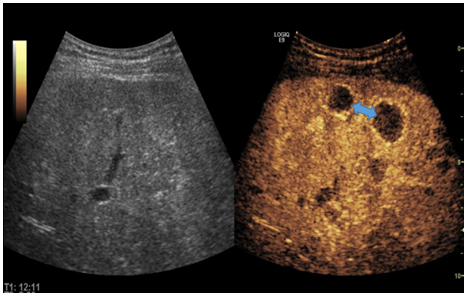

李先生今年45岁,因腹部胀满、疼痛长达一个月,来到德州市第二人民医院就诊。经核磁检查发现,肝右叶有结节,门诊建议进一步检查或穿刺活检明确诊断。随后,李先生做了常规超声检查,但未显示出肝内结节,医生建议行超声造影引导下穿刺活检。在征得李先生同意后,超声医学科主任石洪柱为李先生做了肝脏超声造影,检查历时10分钟,过程中无不适反应。通过超声造影检查发现了肝脏结节,符合恶性肿瘤表现,在超声造影引导下行结节穿刺活检术,最终为李先生明确诊断为肝细胞癌。

石洪柱介绍,超声造影可在常规超声检查的基础上,通过静脉注射超声造影剂,来增强人体的血流散射信号,实时动态地观察组织的微血管灌注信息,以提高病变的检出率,并对病变的良恶性进行鉴别,是一项新型无创的医学影像学技术,被誉为超声发展史上的“第三次革命”。

德州市第二人民医院超声医学科采用的是目前国际上最先进的肝脏超声造影剂——注射用全氟丁烷微球,进行肝脏超声造影检查和引导下穿刺。注射用全氟丁烷微球是针对肝内巨噬细胞特点及肝肿瘤的血液供应特点研制的造影剂,在肝脏肿瘤诊断与鉴别诊断方面有独特的效果,被业界称为“独特肝脏超声造影”。